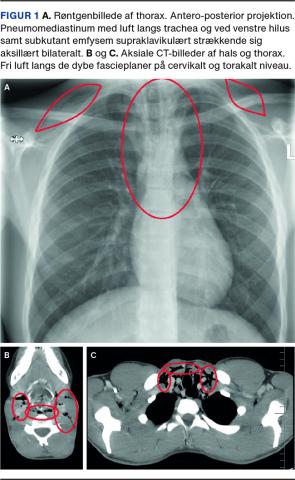

Den objektive undersøgelse inklusive fiberlaryngoskopi viste kun emfysem på halsen og fravær af Hammans tegn. De vitale værdier var alle i normalområdet. Røntgen af thorax viste pneumomediastinum med fri luft langs trachea og venstre hilus samt subkutant emfysem supraklavikulært strækkende sig aksillært bilateralt (Figur 1).

På mistanke om perforation af øsofagus eller trachea blev der foretaget CT af thorax. Der sås pneumomediastinum og emfysem på halsen, men ingen perforation eller anden ætiologisk forklaring. Patienten blev henvist til pædiatrisk vurdering, hvor man pga. spontan bedring i tilstanden og god almentilstand vurderede, at patienten kunne følges ambulant med kontrol en uge efter. Ved denne kontrol var patienten symptomfri, og en kontrolrøntgenundersøgelse af thorax viste normale forhold. Der har ikke været recidiv af symptomer eller objektive fund siden.